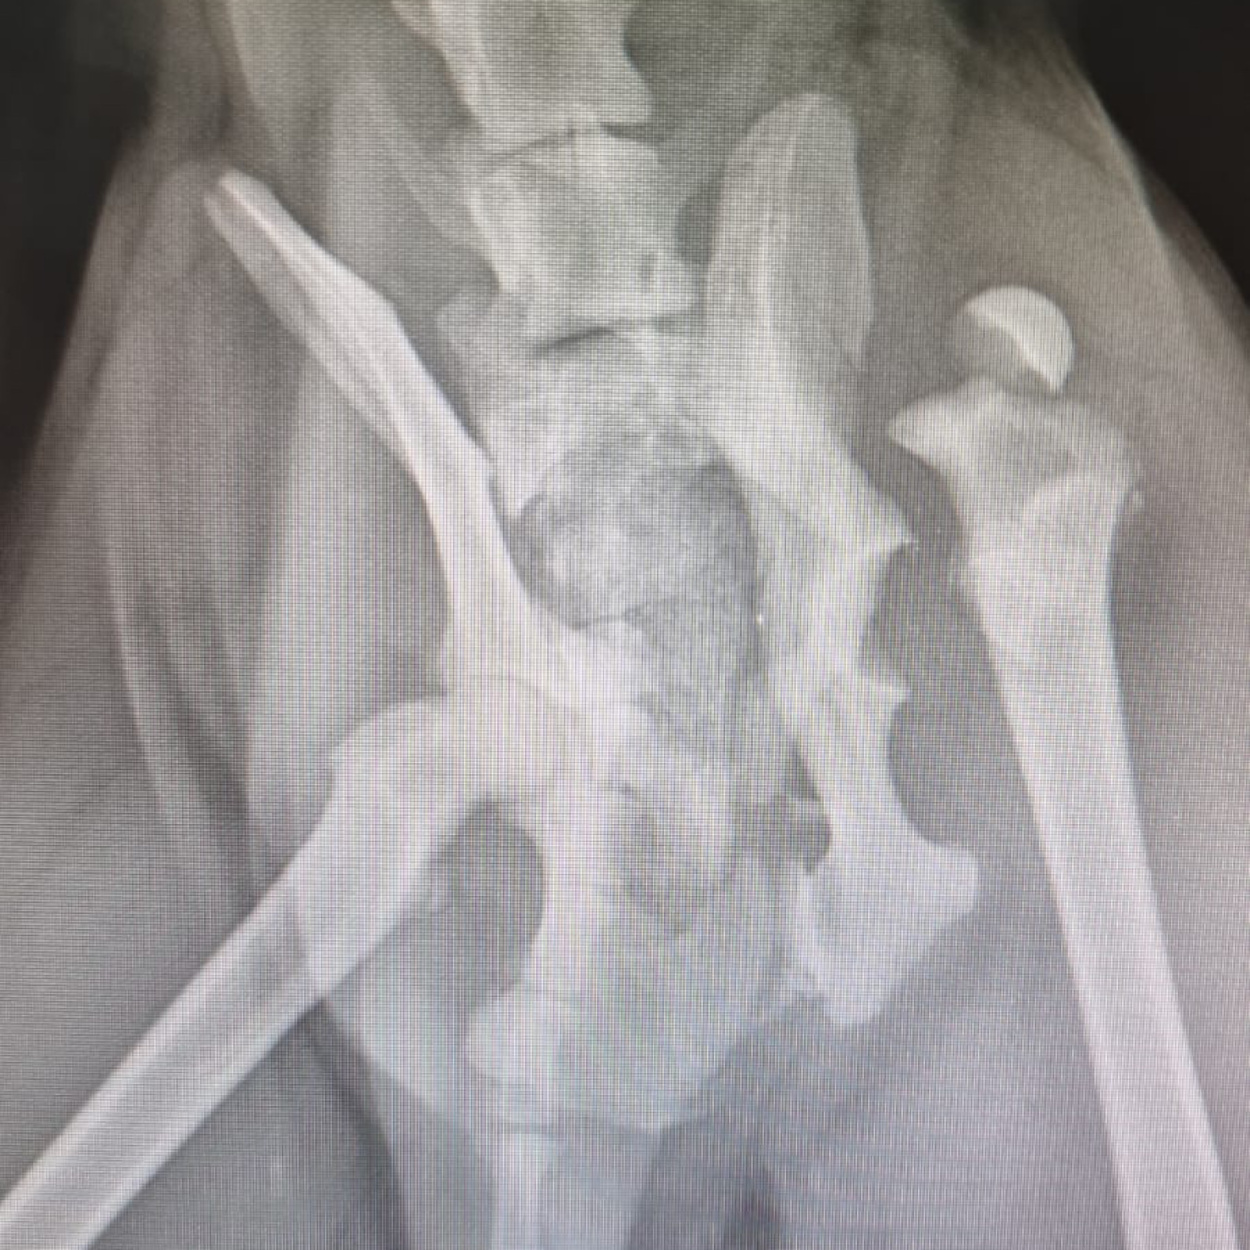

Hope konnte geröntgt werden. Was man nun sieht, tut einem schon vom hinsehen weh...

Das Gute: mit den Bildern wissen wir nun, was genau los ist und dementsprechend, was zu tun ist.

Derzeit wird ein Transport organisiert. Dann gehts für Hope voraussichtlich am Sonntag ab nach Phuket, wo man sie dann hoffentlich operieren kann.